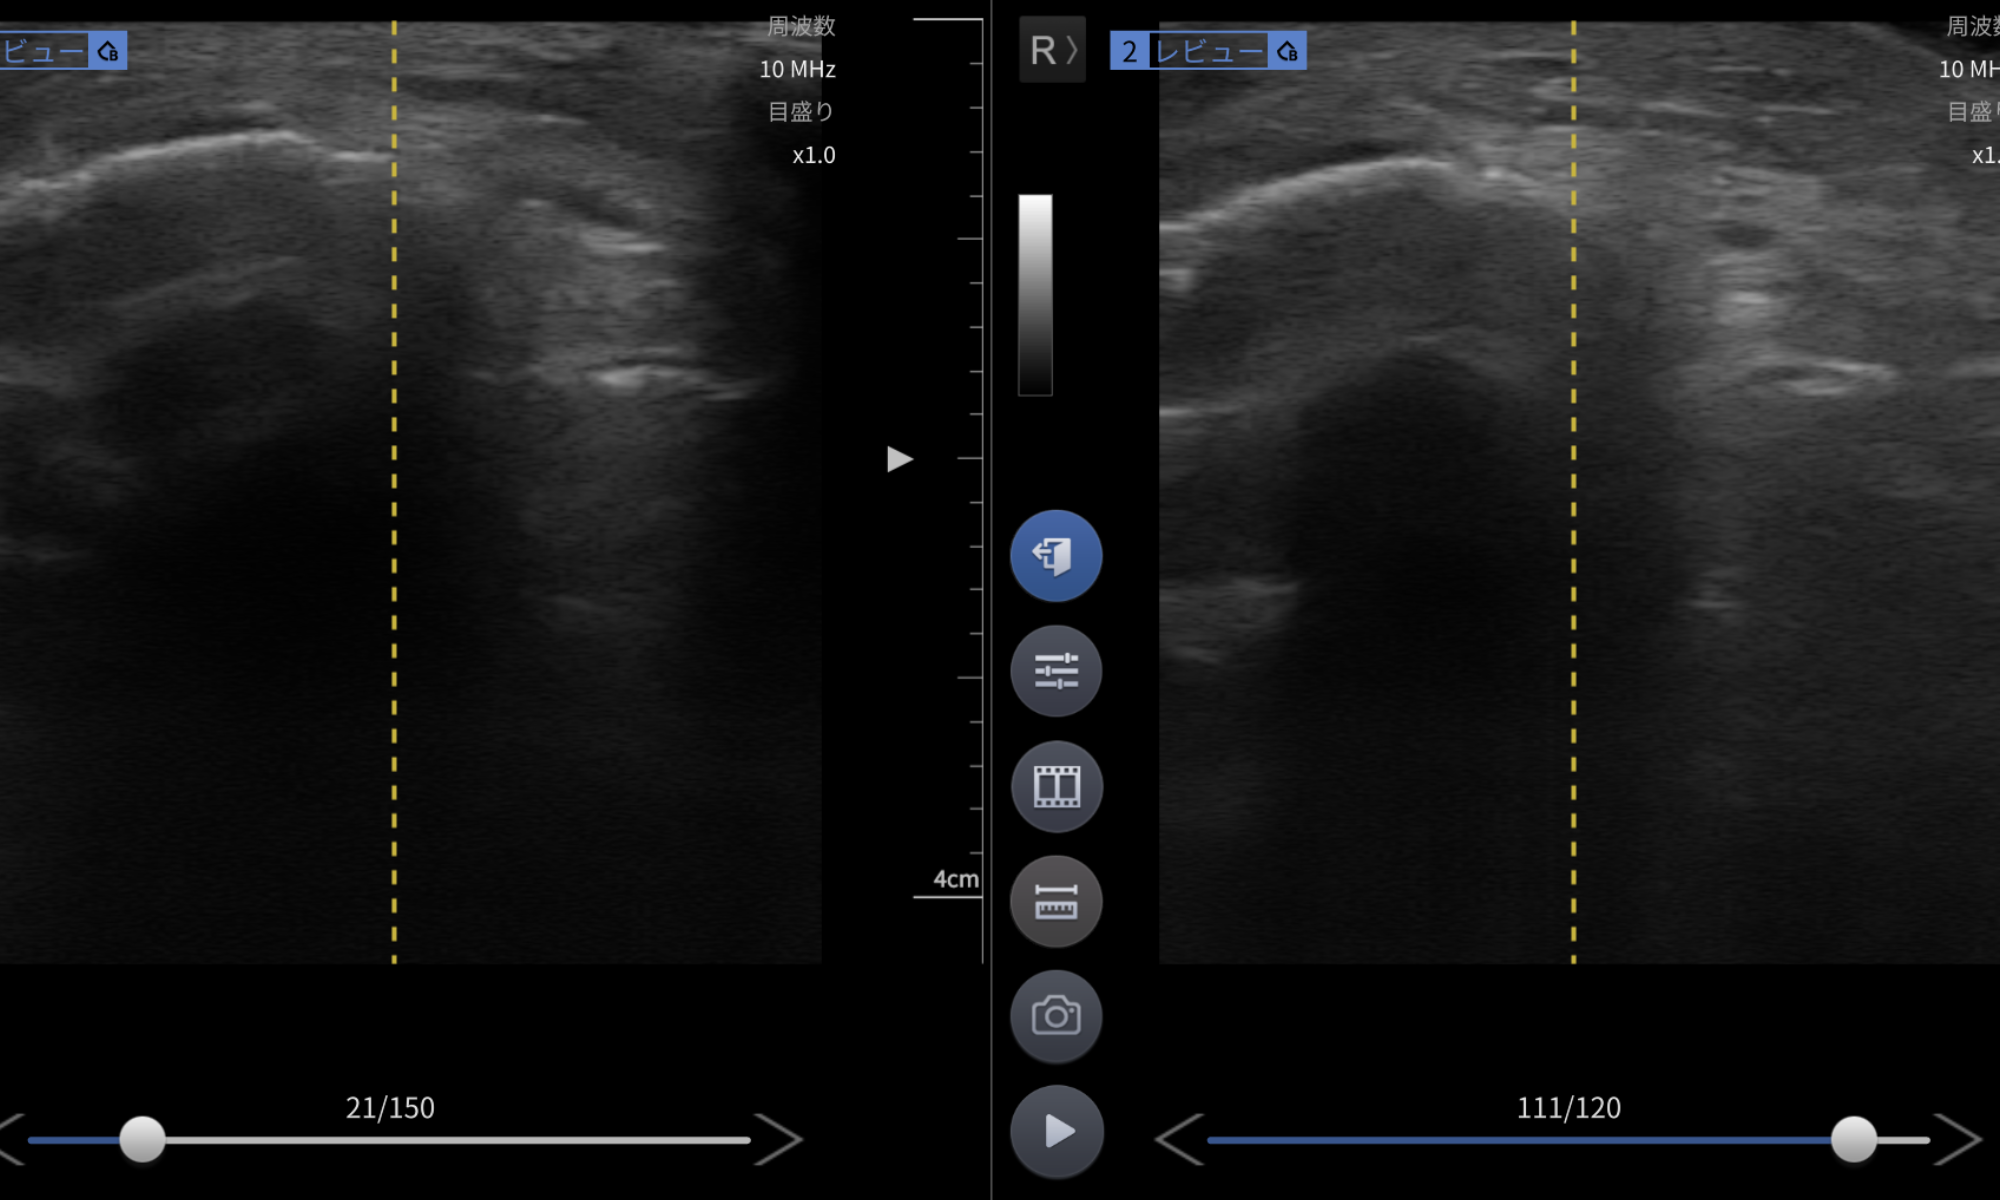

本症例では、毎日20分のLIPUSを継続したことで、約2週で骨癒合良好所見を確認でき、早期の可動域訓練へ移行することが可能となりました。

- エコーで骨癒合良好